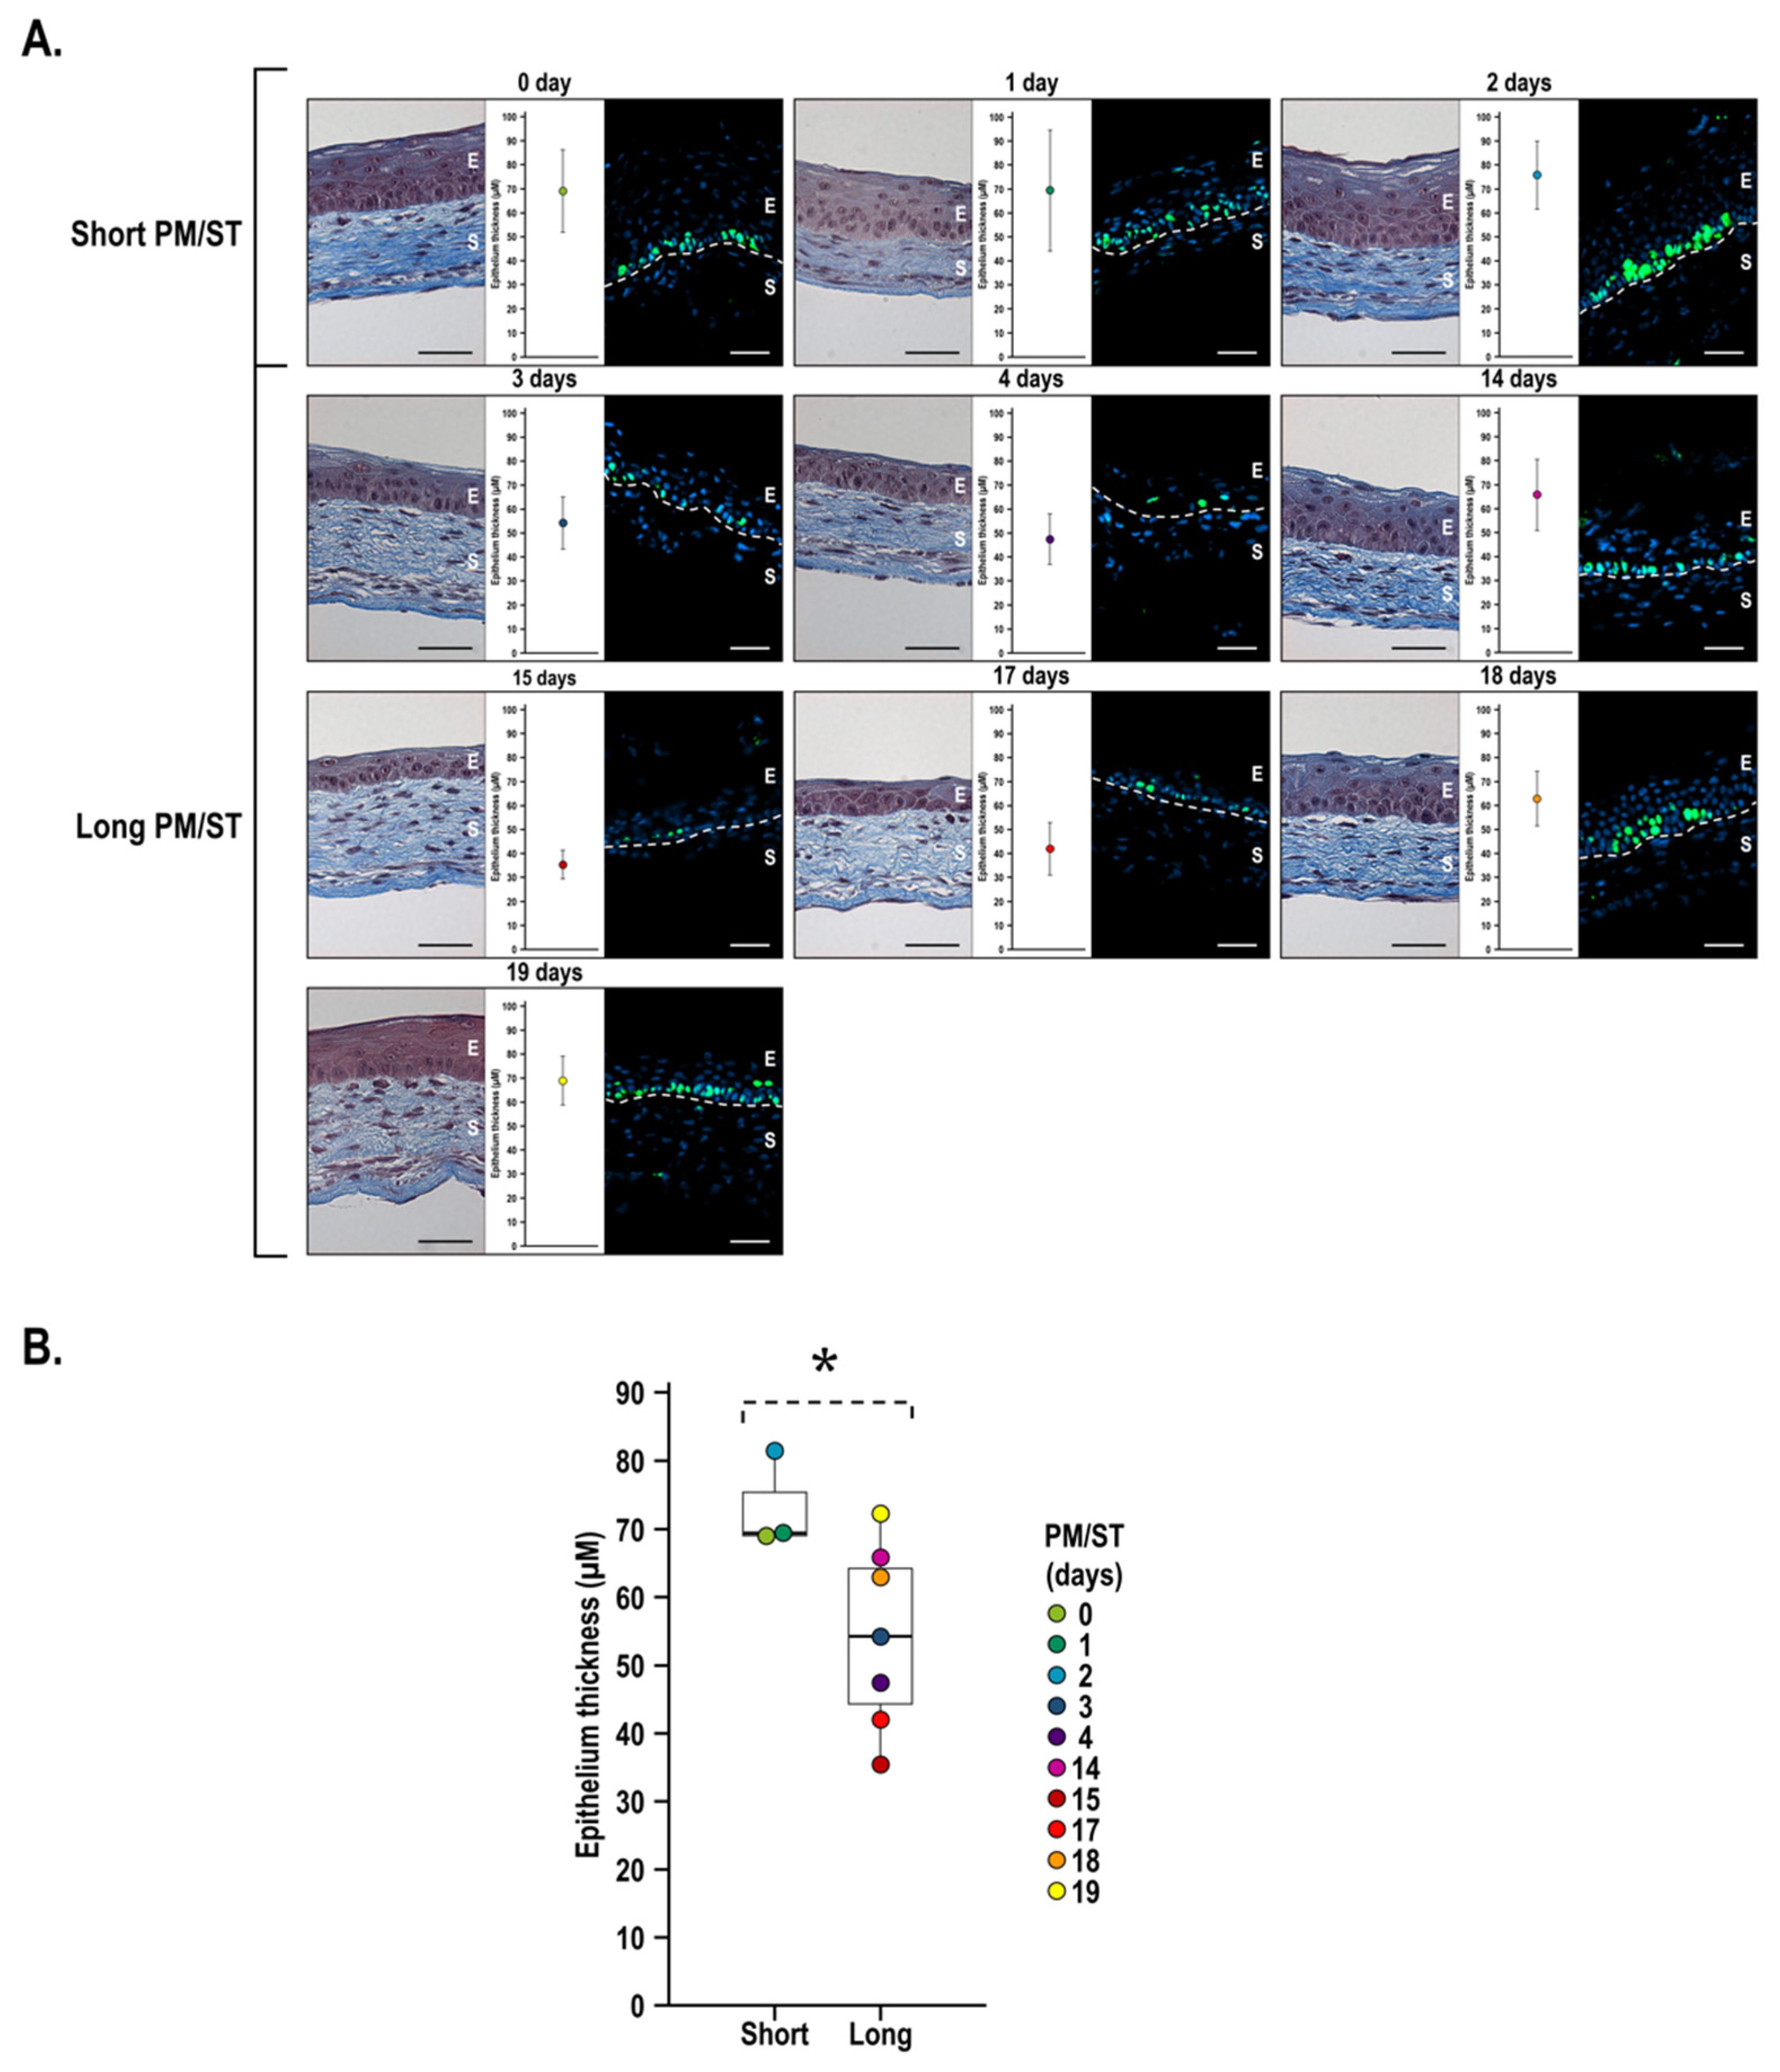

3.5. Morphology and Thickness of the Stratified Corneal Epithelium When Short and Long PM/ST hLECs Are Used for the Production of Human-Tissue-Engineered Corneas (hTECs)